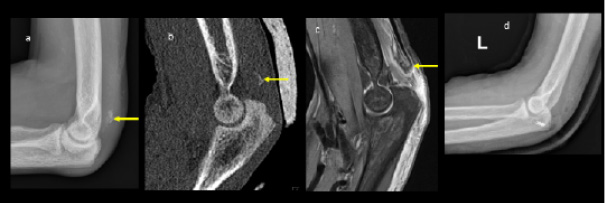

Plain radiographs showed significant bilateral olecranon soft tissue swelling with faint curvilinear ossification proximally suspicious for bilateral avulsion fractures. The ultrasound confirmed loss of tension of the triceps tendon attached to a small bone fragment on the right (Figures 1 and 2). Pelvis radiographs showed an avulsion fracture of the lesser trochanter of the left femur and marked bony sclerosis consistent with renal osteodystrophy. CT of the left elbow indicated a small bony fragment in the distal triceps tendon area with cortical irregularity and significant soft tissue swelling. CT pelvis revealed diffusely increased bone density, subchondral erosions, and resorption at the sacroiliac joints as well as femoral necks consistent with secondary hyperparathyroidism due to end-stage renal disease. MRI of the hip showed generalized skeletal sclerosis along with avulsion of the left iliopsoas tendon with proximal retraction and adjacent soft tissue oedema (Figure 3).

The overall diagnosis included bilateral triceps avulsion fractures with minimal retraction on the right side and significant retraction on the left, a left iliopsoas tendon avulsion with retraction, and florid features of renal osteodystrophy associated with ESRD. The patient underwent surgical repair of the left olecranon avulsion fracture (Figure 1d) while the right olecranon and left lesser trochanter avulsion fractures were managed conservatively.